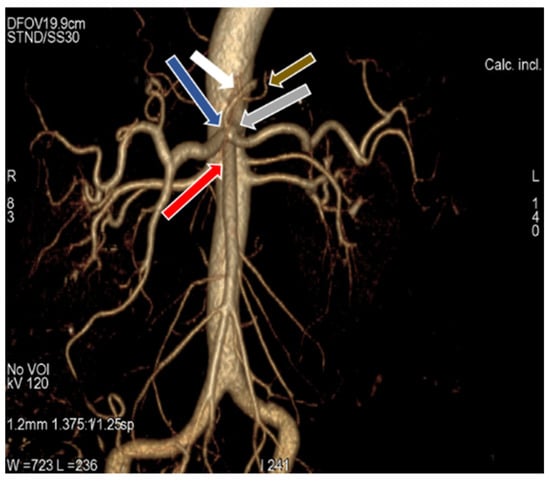

3.1. Variation in Origin and Branching Pattern of Celiac Trunk